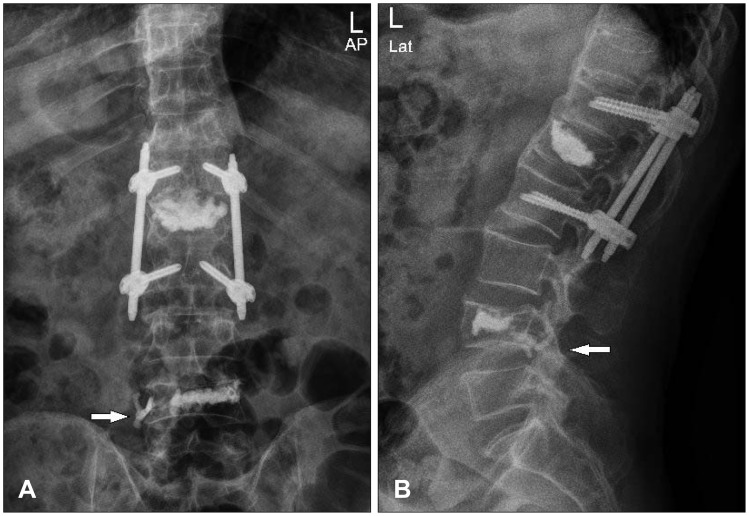

FIGURE 1.

Lumbar spine plain images were taken after L4 vertebroplasty. Anterior-posterior (AP) view (A) and lateral view (B) show that cement leakage spread along the posteroinferolateral margin of L4 vertebra (arrow).